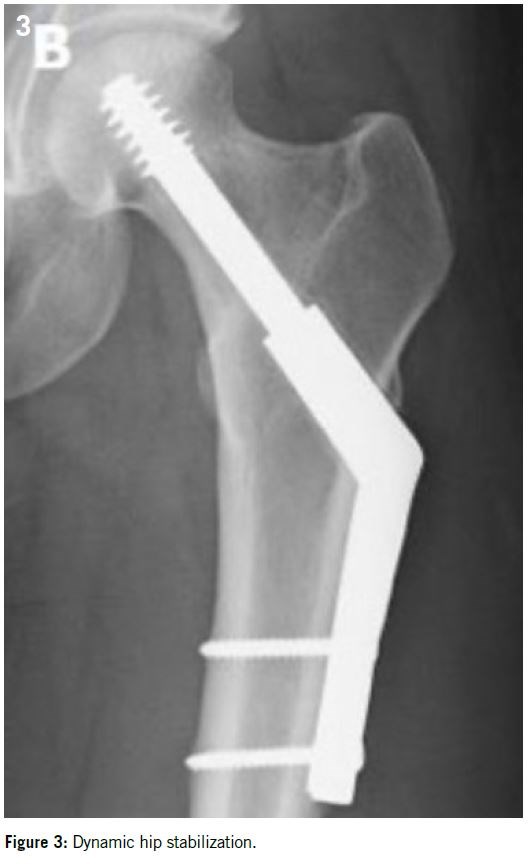

Fracture of the femoral neck: 5% of all BSF. It occurs more frequently in young sportswomen, runners, and military recruits2,24. It can be influenced by certain risk factors such as rapid muscle mass loss combined with a high level of training, decreased femoral bone mass density, gluteus medius weakness, coxa valga, or femoro-acetabular impingement9,18,26,32.

Patients usually complain of hip, inguinal or proximal thigh pain. Pain may be provoked by a single leg hop.

X-rays are positive in only 15% of cases in the early stages, so MRI is the imaging of choice showing the fracture at the superior cortex (tension side) or inferior cortex (compression side) associated with bone marrow edema.

Superior cortex fractures are particularly at risk of displacement so simple fixation by percutaneous screwing can be considered. Generally, three 6.5 mm diameter cancellous screws are placed under fluoroscopic control. In more advanced cases or in heavier or overweight patients, a more sturdy fixation such as a dynamic hip screw may be proposed14 (Figures 2 and 3).